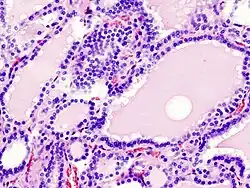

Hyperplasie

Klinisch: hyperthyreoïdie

Hyperplasie is de vergroting van een bepaald orgaan of weefsel als gevolg van een buitengewoon hoge celdeling. Hyperplasie is een reactie op een bepaalde prikkel en verschilt van hypertrofie, doordat bij cellulaire adaptatie de omvang van de cellen niet toeneemt, alleen het aantal cellen.

Hyperplasie tast zowel het parenchym als het interstitium aan. Het kan zowel fysiologische als pathologische oorzaken hebben, zoals een ontsteking of endocriene ziekte. Het kan ook een compensatie voor een vergroeiing of verwonding elders in het lichaam zijn.